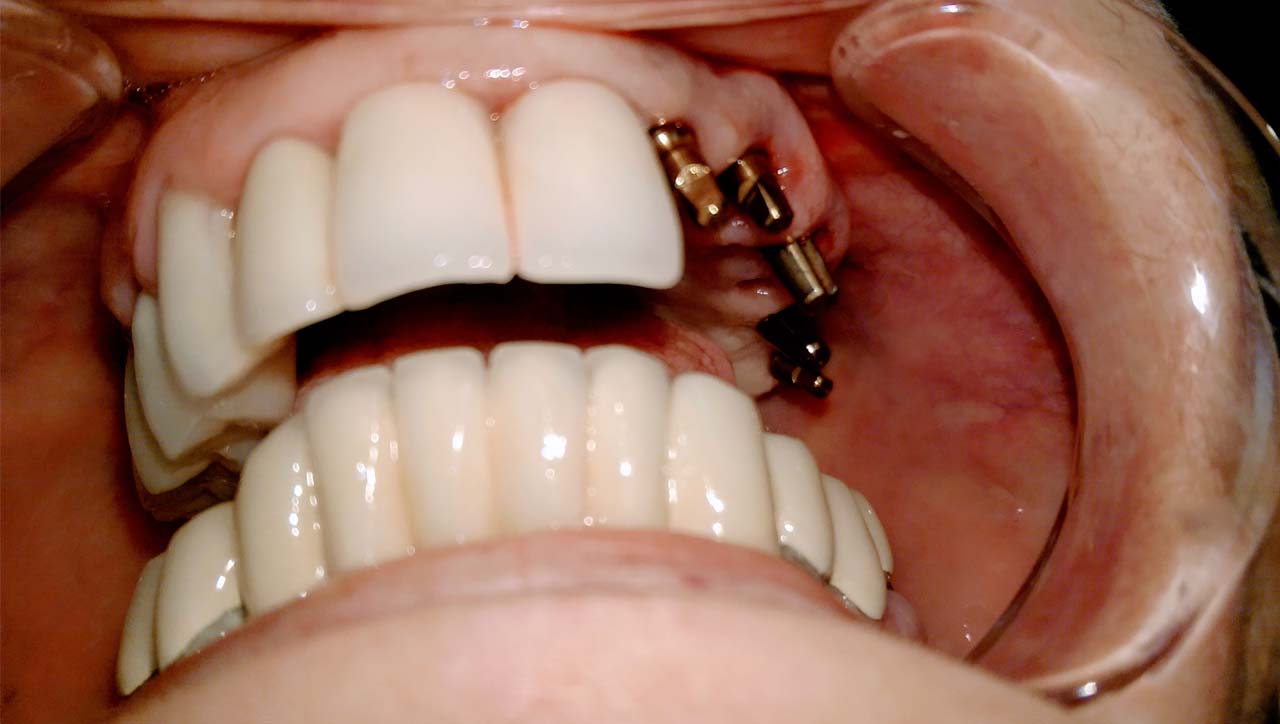

Elhanyagolt fogsor cseréje 2 nap alatt

2 nap alatt varázsoltuk ezt a szép esztétikus alsó, felső körhídat implantátumokkal megtámasztva a korábban elhanyagolt szájba. Az 1. nap 26 fogat távolítottunk el, mert annyira rossz állapotban voltak, és rögtön azonnal terhelhető IHDE svájci implantátumokat raktunk be, fentre 8, lentre 6 darabot. A sebeket összevarrtuk és intraorális szkennerrel digitális lenyomatot vettünk. 2 nap múlva pedig beragasztottuk a kész PMMA műanyag körhidakat. Dr. Kelemen Péter és a Symbion Fogtechnika munkája.